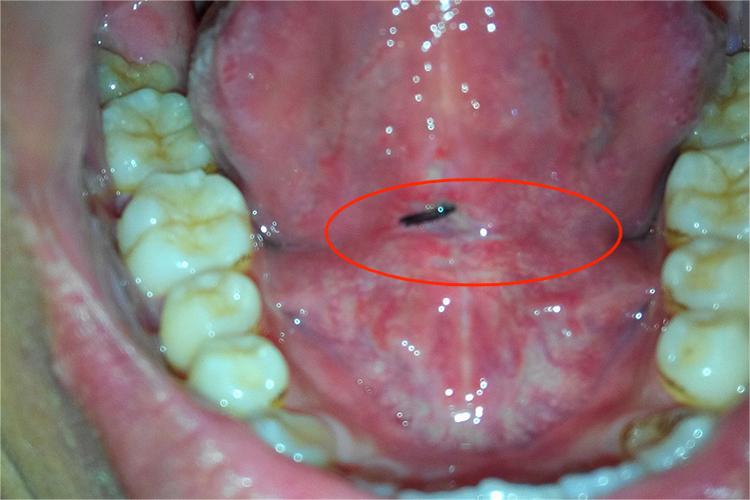

舌系带为舌下面黏膜在中线上折成的皱襞。断裂严重,常见于外伤损伤舌体引起。

舌系带断裂严重,可表现为舌系带与舌体完全断裂或接近完全断裂的形态,一般伴随大量出血,患者自觉疼痛感剧烈。并且由于舌系带损伤,患者可能会出现影响说话及进食的情况,严重者可出现舌后坠。如果出血较多未能及时处理可能会出现窒息的情况。